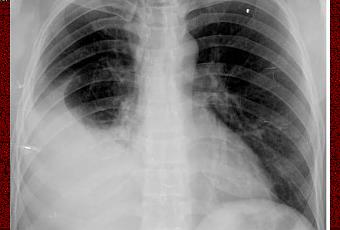

El diagnóstico del un derrame pleural se realiza por lo general mediante radiografía, donde los signos son visibles cuando el volumen es mayor de 75 ml., teniendo en cuenta que los valores normales de líquido están entre los 5 y 15 ml.